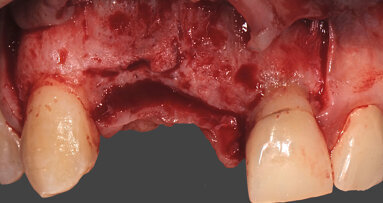

Dopo l’anestesia locale, è stato scollato un lembo a spessore totale e il dente estratto in modo atraumatico (Fig. 1). Successivamente, l’alveolo post-estrattivo è stato zeppato con granuli di osso bovino decellularizzato (Re-Bone®, Ubgen, Padova/Italy) e utilizzata una membrana di pericardio bovino come barriera (Shelter® Membrane, Ubgen, Padova/Italy) (Fig. 2).

I lembi sono stati poi suturati a livello dell’osso (Gore-Tex®, 4.0, Gore, Newark/ NJ, USA) senza la necessità di ottenere una chiusura completa (Fig. 3). In fase postoperatoria è stato prescritto un antinfiammatorio (Nimesulide 100 mg, 2 volte al giorno per 3 giorni), un analgesico (Paracetamolo 500 mg, 1 compressa ogni 8 ore per 3 giorni) e clorexidina 0.12%, e fornita istruzione completa all’igiene orale. La sutura è stata rimossa dopo 10 giorni. A 3 e a 6 mesi sono state eseguite le radiografie periapicali parallele.